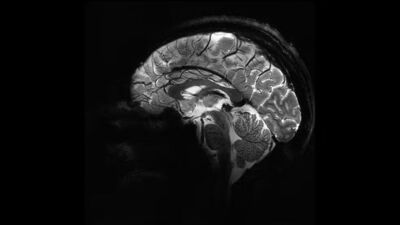

İnsan beyninin en net görüntüsü yayınlandı

Fransa Atom Enerjisi ve Alternatif Enerjiler Kurumu (CEA), dünyanın en güçlü manyetik rezonans görüntüleme (MRI) cihazıyla elde edilen, insan beyninin en net görüntüsünü yayınladı. CEA'dan yapılan yazılı açıklamada "Iseult" adlı MRI cihazıyla çekilen beyin görüntüsünün 20 yıldan uzun süren bir çalışma sonucu elde edildiği belirtildi.

Yapılan çalışmalar kapsamında MRI cihazının son birkaç ay içerisinde yaklaşık 20 sağlıklı gönüllü üzerinde test edildiği kaydedilen açıklamada, neredeyse 4 dakikada en net beyin görüntüsünün elde edildiği aktarıldı. Açıklamada, 11,7 Tesla manyetik güce sahip Iseult MRI makinesiyle kısa sürede çekilen görüntülerin, hastanelerde yaygın kullanılan cihazlarla elde edilmesinin saatler sürebileceği kaydedildi.

Iseult Projesi Başkanı ve CEA Araştırma Direktörü Nicolas Boulant, yaptığı açıklamada, verilerin daha yüksek kalitede elde edilebilmesi için araştırmanın birkaç yıl daha devam edeceğini belirterek, hedeflerinin 2026-2030’a kadar nörodejeneratif hastalıkların yanı sıra şizofreni ve bipolar bozukluğu gibi psikiyatri alanındaki birçok hastalığı araştırmak olduğunu ifade etti.

Iseult MRI cihazı ile elde edilen ultra detaylı anatomik bilgilerin, Alzheimer ve Parkinson gibi hastalıkların teşhisinde yardımcı olması bekleniyor.